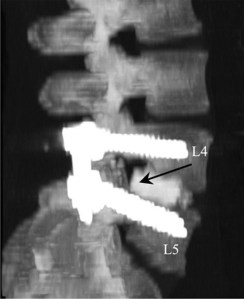

El canal medular estrecho es la causa más frecuente de intervenciones quirúrgicas en nuestro país. En las consultas del médico rehabilitador cada vez son más frecuentes los pacientes con complicaciones postquirúrgicas (lesiones medulares, fibrosis postquirúrgicas con síndromes radiculares, errores de la osteosíntesis, infecciones postquirúrgicas ), que hacen que nos planteemos si realmente debe de intervenirse a tantos pacientes.